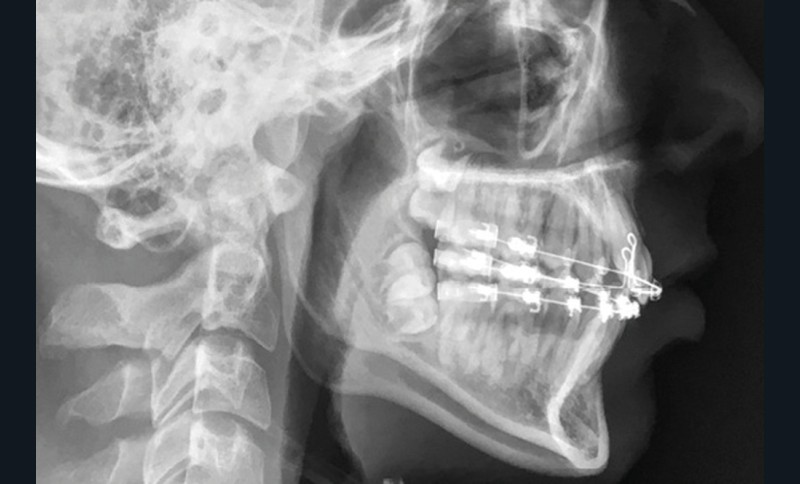

L’analyse de la téléradiographie de profil (fig. 1g) confirme une classe II squelettique à tendance hyperdivergente avec une normo-position de l’incisive mandibulaire dans sa symphyse. L’âge du patient et la croissance mandibulaire en rotation postérieure (travaux de Björk) ne permettront sans doute pas une correction de la classe II squelettique sans version de l’incisive mandibulaire.